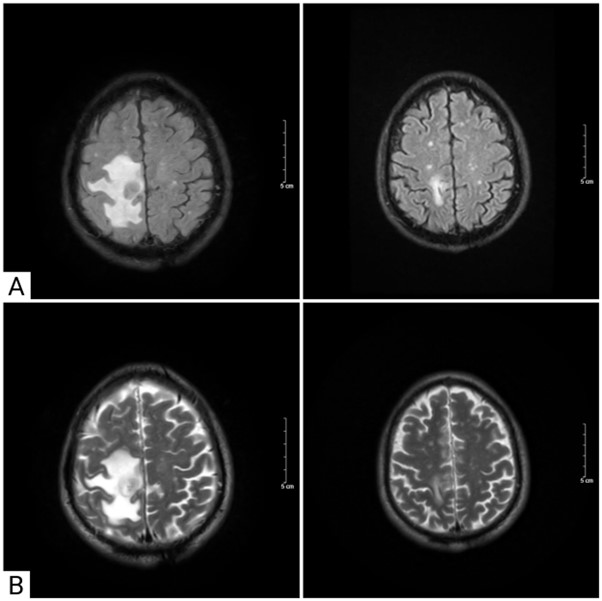

Hình 4. So sánh hình ảnh chụp cộng hưởng từ sọ não trước và sau điều trị xạ phẫu bằng dao gamma và điều trị toàn thân

A. Hình ảnh chụp cộng hưởng từ sọ não trên chuỗi xung FLAIR: Khối u thuỳ trán phải giảm kích thước từ 18x18mm xuống còn 8x10mm

B. Hình ảnh chụp cộng hưởng từ sọ não trên chuỗi xung T2: Khối u não ở thuỳ trán phải giảm kích thước sau điều trị